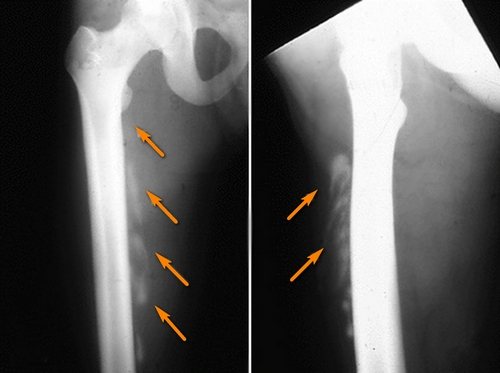

В постановке диагноза подобного увечья компетентен врач. Потребуется провести диагностику больного, прощупать пострадавшую область и возле неё, проверить суставы на движение. Если при осмотре врач заподозрил тяжёлую травму, к примеру, перелом бедра, он вправе назначить рентгенографию или МРТ для осмотра мягких тканей.

После осмотра доктор назначает рентгенографию, с помощью которой определяет присутствие или отсутствие перелома или вывиха. Для более детального обследования рекомендуется проведение КТ или МРТ, чтобы выявить разрыв соединительной ткани, кровоизлияние внутри бедренной мышцы или отслоение внутренних слоев кожи.

Диагностируют оссифицирующий миозит по кораллоподобным теням в мышцах на рентгенограмме. Если надавить на эти места, можно почувствовать некоторое уплотнение, а больной ощутит боль. В дальнейшем эти «коралловые облачка» превращаются в единую плотную ткань.

В обязательном порядке проводят рентгенографическое исследование, чтобы распознать перелом бедра или определить наличие трещин. При более серьезном повреждении делают магнитно-резонансную томографию, которая более точно визуализирует мягкие ткани и определяет внутренние гематомы, разрывы мышц бедра, отслоение подкожной клетчатки.